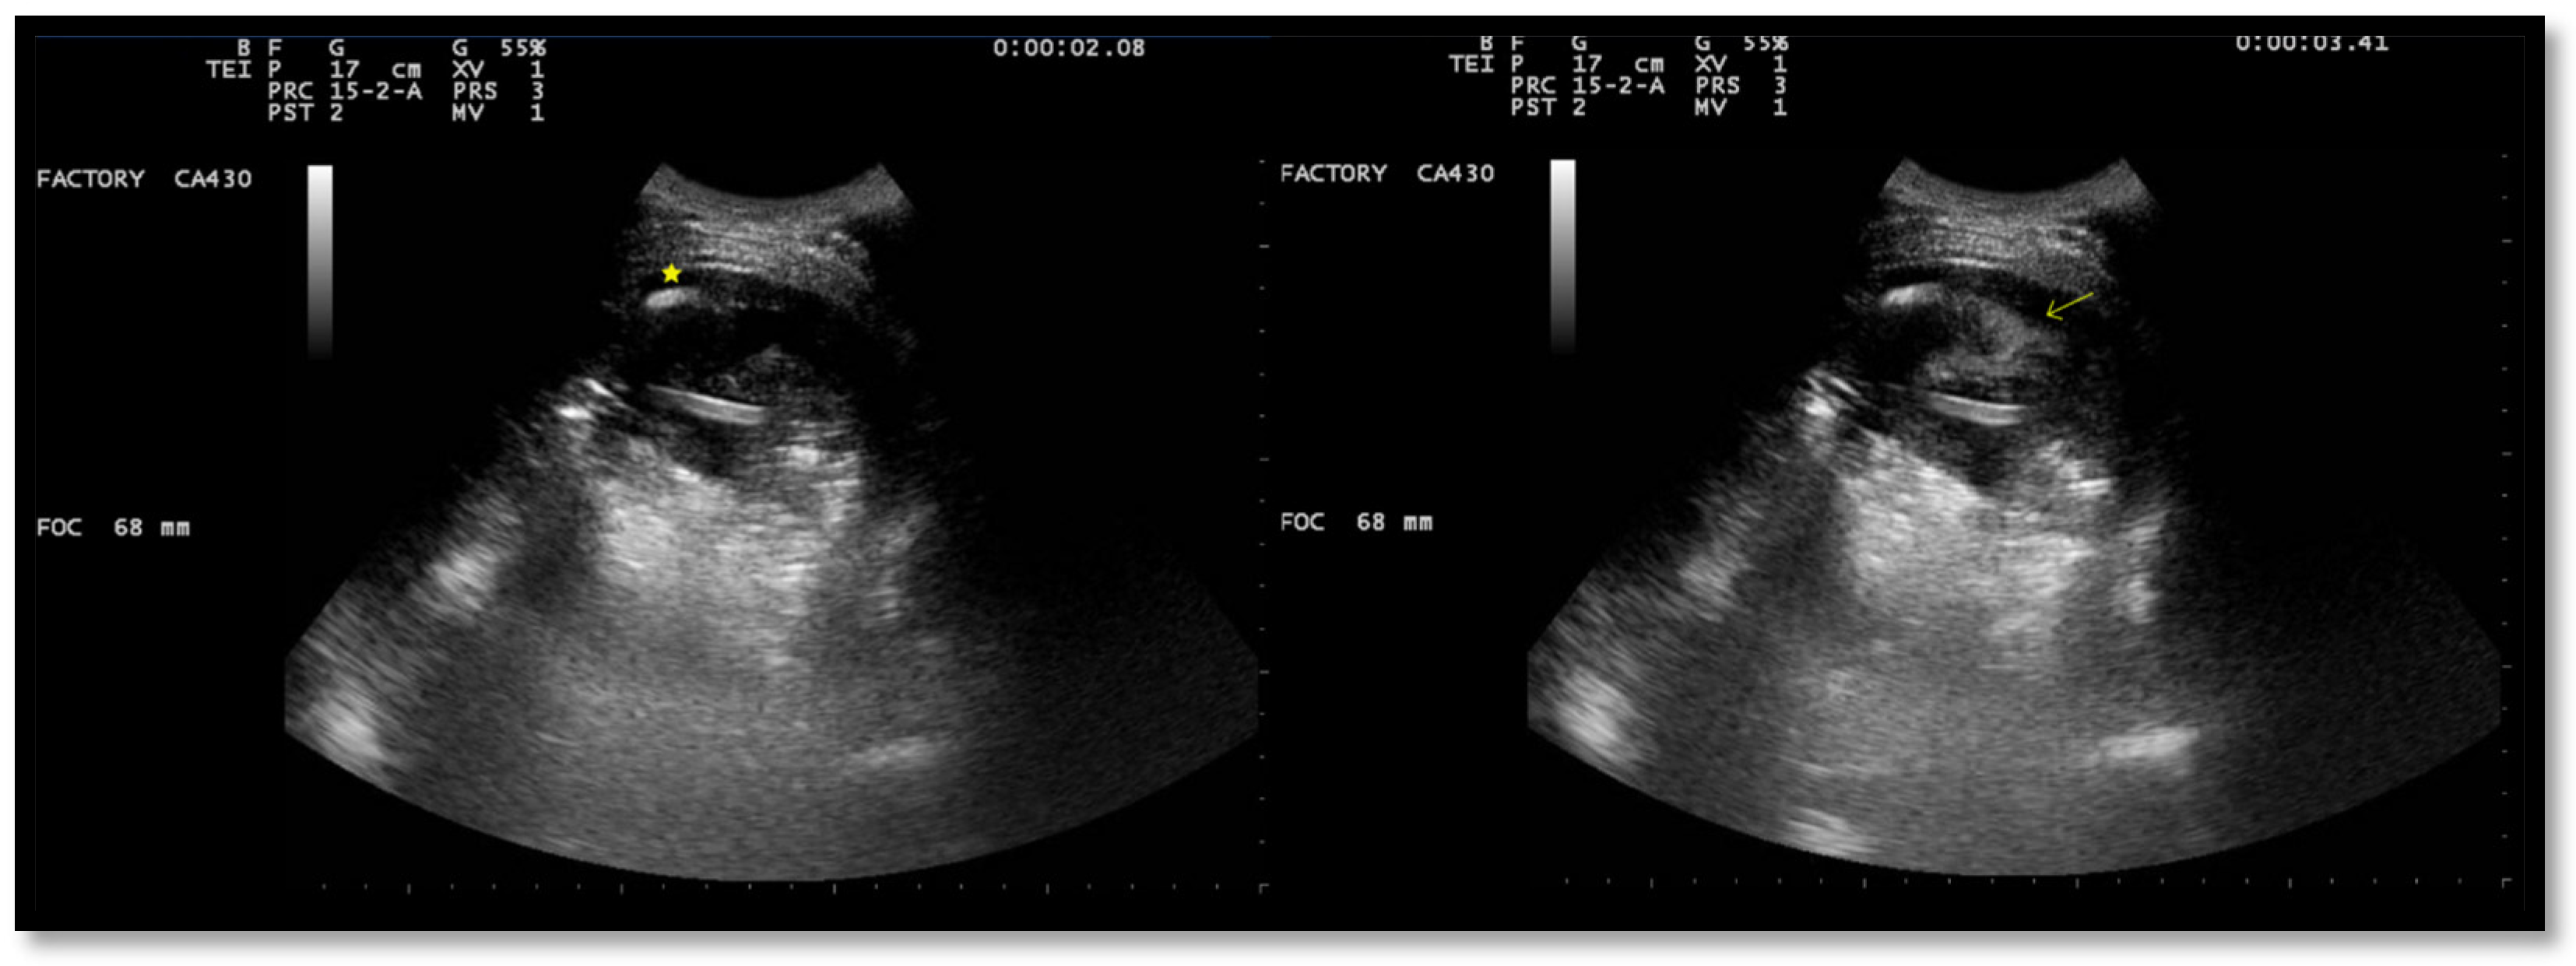

After the placement of a chest tube, pleural fluid samples were sent for microbiological and physicochemical analysis, which confirmed the diagnosis of pleural empyema. Two days after the placement of the chest tube, the fluid flow decreased. To break up the fibrin pockets present in the empyema and promote the complete evacuation of the fluid, irrigation of the pleural cavity with 200,000 UI of urokinase in 50 mL of saline solution was performed under US guidance (Figure 2).

Immediately following the instillation of the fibrinolytic agent, the chest drain was clamped for approximately 4 h. Then, irrigation with a few ml of saline solution was performed, and the chest tube was reopened. US observations 24 h after the intrapleural fibrinolysis showed a marked reduction in the extent of the effusion and localizations (Figure 3). After 72 h, the remaining fibrin sprouts had completely disappeared (Figure 3). This facilitated the drainage of the remaining exudate. At the same time, there was an improvement in his clinical condition with the disappearance of his fever and the restoration of normal oxygenation, which led to the discontinuation of oxygen therapy.

Figure 1. Chest US at admission. Multiloculated pleural effusion.

Figure 2. Chest US during pleural lavage with urokinase. Star: distal end of chest drain; Arrow: spread of fluid.

Figure 3. Chest US 48 h (left) and 72 h (right) after intrapleural instillation of urokinase.